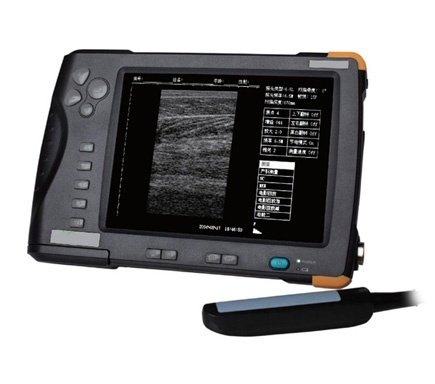

Portable Veterinary Ultrasound Scanner 2-10MHz Waterproof SIFULTRAS-4.2

Portable Veterinary Ultrasound Scanner 2-10 MHz Waterproof SIFULTRAS-4.2

- Image smoothing, filtering, edge enhancement, frame correlation, linear interpolation, and other processing, the image is crisp and clear in high resolution.

- 7-inch TFT screen.

- Small and lightweight (at-home ultrasound).

- Display size: 7-inch TFT.

- Overall size: 216mm×147mm×27mm.

- Total weight: 950g(with battery).